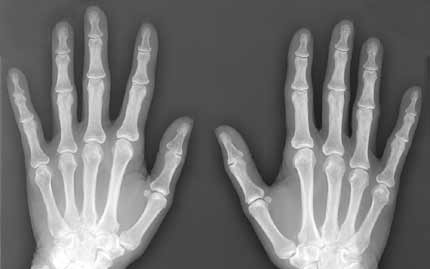

A magzatvízben lévő őssejtek újjáéleszthetik az öregedő és gyenge csontokat - állítják brit kutatók, akik szerint felfedezésük segíthet genetikai betegséggel született gyerekeken, idős embereken és űrhajósokon is.

A londoni Great Ormond Street Hospital és a University College London együttműködéséből született Gyermekegészségi Intézet szakemberei súlyos genetikai betegségben, üvegcsontúságban (osteogenesis imperfecta) szenvedő egerekbe fecskendezték be a mintákból kinyert őssejteket.

Az emberek esetében nagyjából minden huszonötezredik csecsemő ezzel a betegséggel, vagyis többszörös csonttöréssel jön a világra. Azok, akik túlélik, a későbbiekben akár évi 15 csonttörést is szenvedhetnek, fogaik törékenyek, hallásuk rossz lehet és fejlődési problémákkal is küzdhetnek.

Az egereken végzett vizsgálatok azt mutatták, hogy az őssejtek befecskendezésével az állatok csontjai megerősödtek, és rugalmasságuk, valamint szerkezetük is javult. A csonttörések száma 80 százalékkal csökkent.

A csontok folyamatos átépüléséért a csontfaló sejtek (osteoclast) és a csontképző sejtek (osteoblastok) a felelősek. Guillot szerint az üvegcsontúság, a csontritkulás és az űrutazásokkor bekövetkező csonttörések hátterében a csontképző sejtek "ellustulása" áll.

Az eredmények szerint a magzatvízből nyert őssejtek növelték a csontképző sejtek természetes aktivitását, ahelyett, hogy közvetlenül maguk hoztak volna létre új csontokat.

A humán teszteket két éven belül elkezdhetik. A kutatók végső célja annak a kiderítése, hogy az őssejtek milyen anyagot engednek szabadon, amely beindítja a csontképző sejteket.